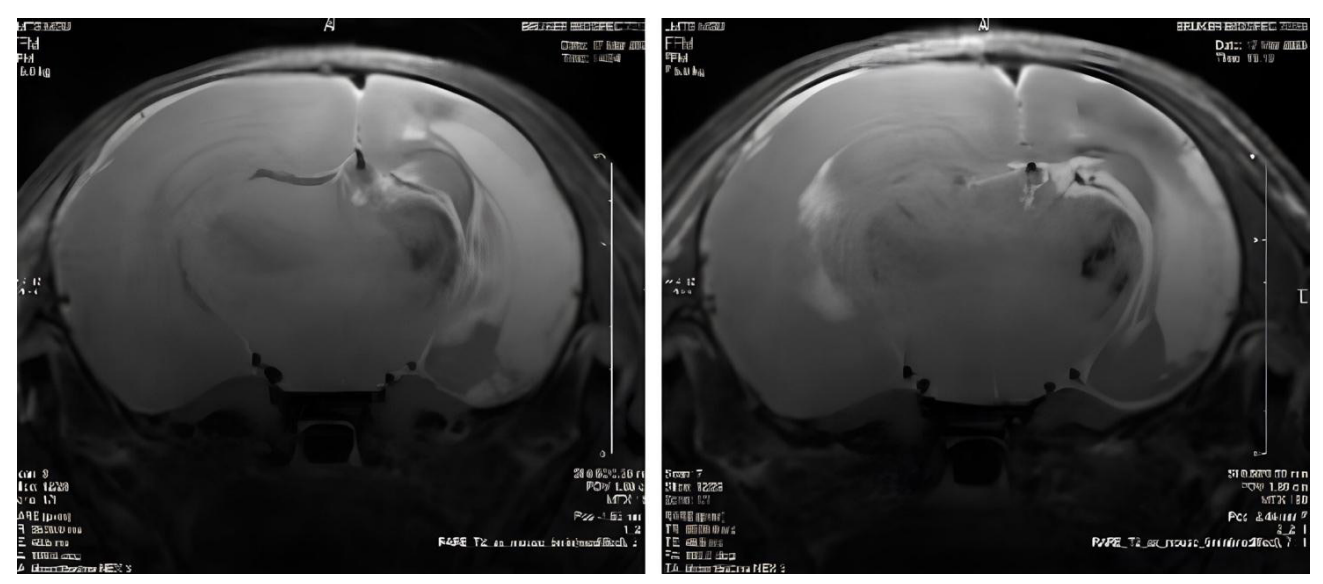

Fig. The animals’ brain MRI scans on day 7. Group C — left, group Xe — right